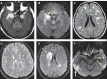

Figures